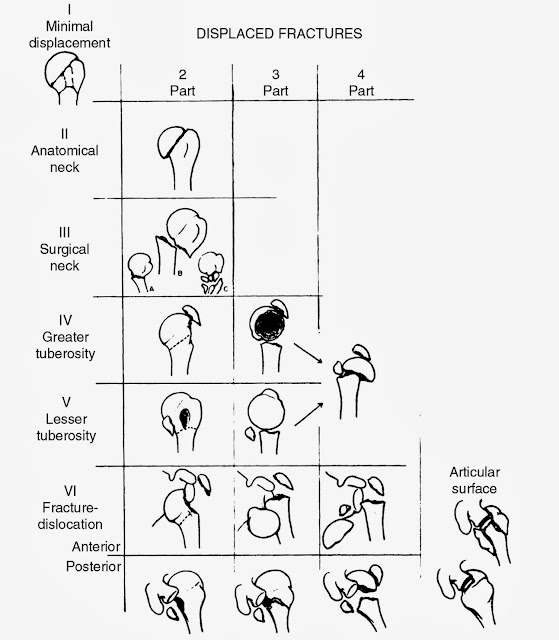

上腕骨近位端骨折におけるneer分類 たくみロドリゲス 運動器理学療法士 Note

上腕骨近位端骨折 一般社団法人 日本骨折治療学会 骨折の解説

上腕骨近位端骨折 一般社団法人 日本骨折治療学会 骨折の解説

上腕骨近位端骨折 じょうわんこつ きんいたん こっせつ 福岡の弁護士による後遺障害 等級認定サポート

肱骨頭骨折 Humeral Head Fractures 小小整理網站smallcollation

最全面的骨折分型匯總 每日頭條

最全面的骨折分型匯總 每日頭條

最全面的骨折分型匯總 每日頭條

最全面的骨折分型匯總 每日頭條

最全面的骨折分型匯總 每日頭條